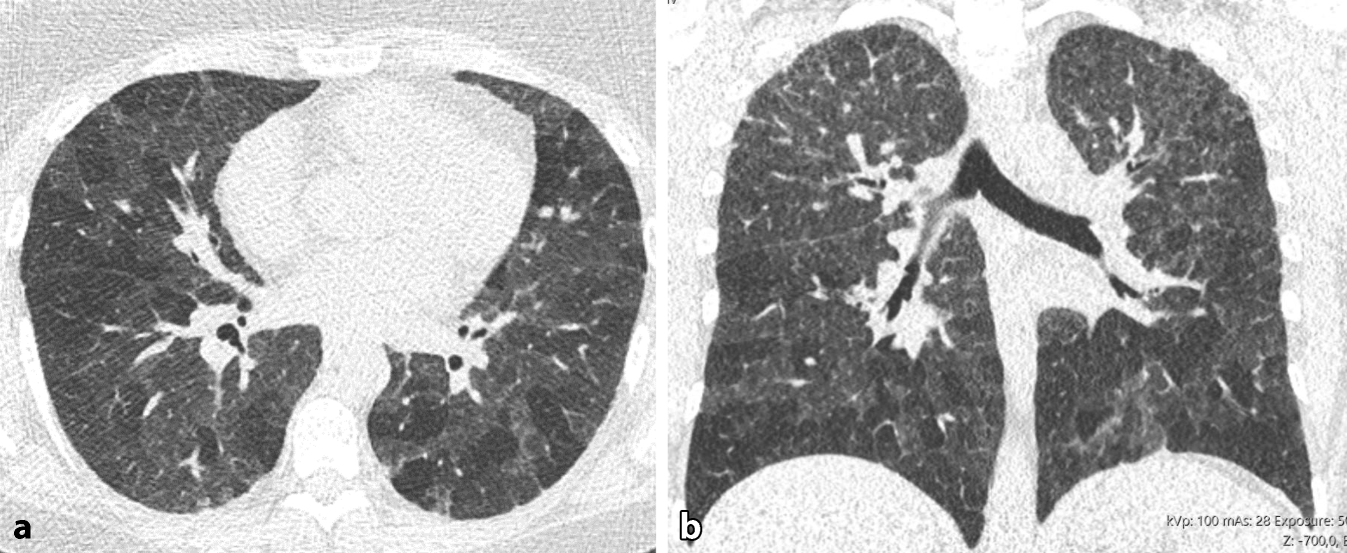

Abb. 5

Fibrotische exogen-allergische Alveolitis (EAA) ohne Inflammation. a Axiale und b sagittale multiplanare Reformation (MPR) einer nativen High-Resolution-Computertomographie (HRCT). Fibrose erkenntlich an irreguläre Retikulationen und Traktionsbronchiektasen. Zudem Air-Trapping. Zeichen einer Inflammation zeigen sich nicht